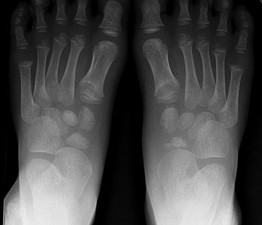

[单选题]男,5岁,足背肿痛,请结合图像,选出最可能的诊断 ( )A.跗舟骨缺血坏死B.跗舟骨骨折C.成骨不全D.软骨发育不全E.剥脱性骨软骨炎

[单选题]男,5岁,足背肿痛,结合图像,最可能的诊断是()A.跗舟骨缺血坏死B.跗舟骨骨折C.成骨不全D.软骨发育不全E.剥脱性骨软骨炎